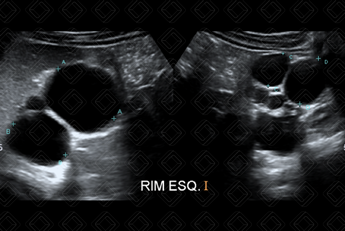

Texto alternativo para a imagem Figura 3. Créditos: Dra. Elazir Mota - Rio de Janeiro/RJ

Texto alternativo para a imagem Figura 4. Créditos: Dra. Elazir Mota - Rio de Janeiro/RJ

Descrição das figuras 3 e 4: Ultrassonografia do aparelho urinário pós-natal confirmando a presença de múltiplos cistos, não comunicantes e tamanhos variados na loja renal esquerda, associado à ausência de parênquima renal deste lado. A avaliação do rim contralateral é de suma importância e, nesse caso, o rim direito encontrava-se normal.

• Ultrassonografia aparelho urinário: E m geral, essas crianças já chegam para o radiologista pediátrico para confirmação da suspeita de rim multicístico displásico no período fetal. O exame de escolha será a ultrassonografia do aparelho urinário, na qual observa-se múltiplas imagens císticas, não comunicantes, de tamanhos variados e sem parênquima renal adjacente. O sistema pielocalicinal e ureter encontram-se ausentes do lado acometido (figuras 3 e 4);